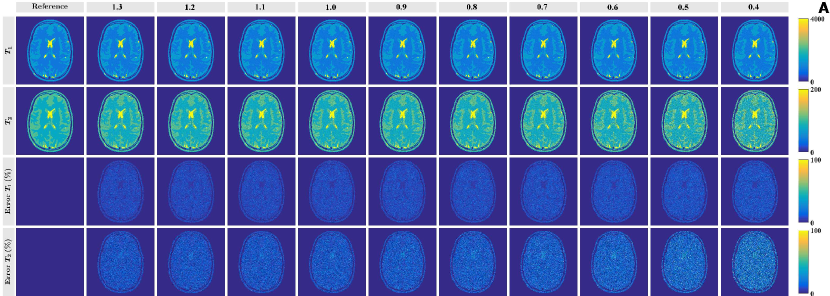

Figure 6 shows the embeddings and color-coded dictionary maps for subdictionaries of , each embedded individually. For small scaling factors the color-coded dictionary map shows less color variation in the dimension, suggesting reduced encoding. This effect is strongest in the right half of the color-coded dictionary maps, corresponding to long values. For scaling factors between 0.8 and 1.3 the embeddings and the color-coded dictionary maps look rather similar, predicting smaller matching errors for high values than for low values. These results are confirmed by simulation results in Figure 11, where the percentage errors are larger for than for . They are furthermore especially pronounced for tissues with long values (CSF) and for low scaling factors. In general these matching errors are much larger than those in Figure 10, showing the advantage of fixing the value in the matching process.